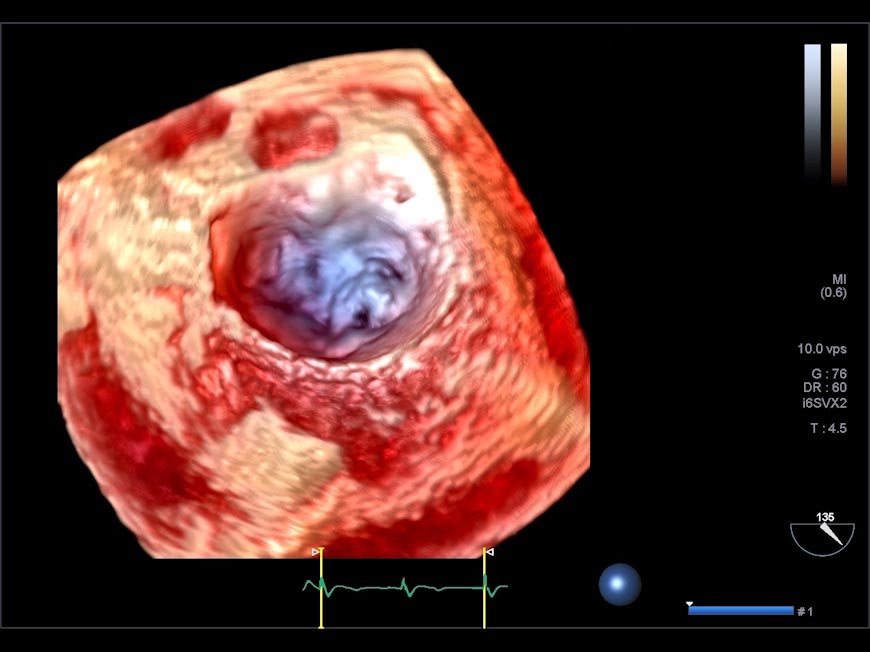

Canon Medical Systems' comprehensive Cardiac Contrast Imaging package.

Contrast Imaging

Allows you to evaluate left ventricular function opacification in difficult-to-image patients.

4D volume imaging for routine clinical use.

4D-TEE / Volume Matrix Transducer* (i6SVX2)

The Aplio i-series volume matrix transducer enables you to acquire high-quality 4D volumes at high frame rate. A host of advanced analysis tools allows for in-depth assessment of cardiac anatomy and function.

*Available on the Aplio i900 only.